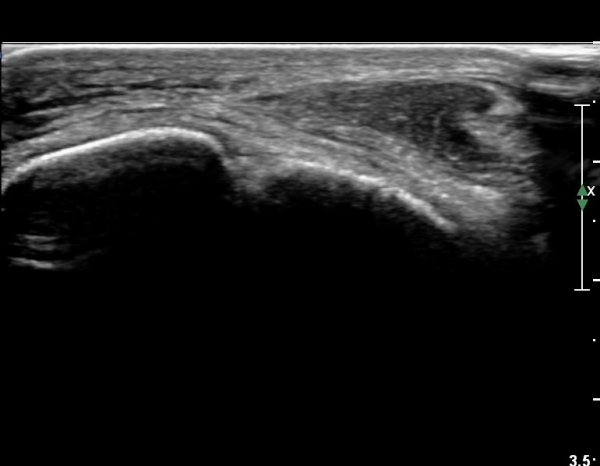

¹ß¸ñ ¾ÕÂÊ Á¾´Ü¸é°Ë»ç¿¡¼­ °üÀý³» ºÎÁ¾À» º¸ÀδÙ(»çÁø 1).

°üÀý³» ºÎÁ¾Àº ½É°¢ÇÑ ¼Õ»óÀ» ¾Ï½ÃÇÏ´Â ¼Ò°ßÀÌ´Ù.